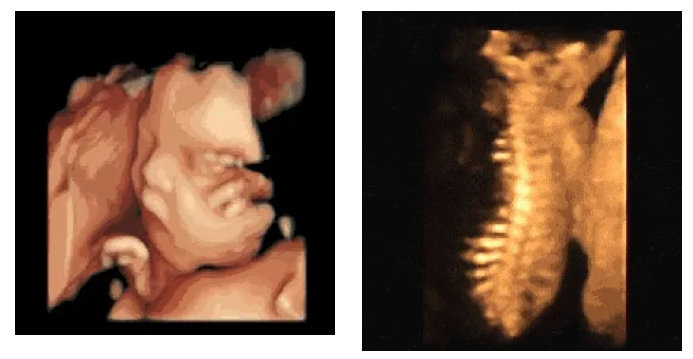

“美国高清GE四维彩超”

美国高清GE四维彩超排畸更精准美国GE系列彩超的先进性秒杀其他彩超系列,拥有安全无辐射、高准确率、高清晰度、高分辨率的优点,在产前排畸、评估宝宝宫内发育情况、妇科不孕症诊疗、评估盆底健康等方面,都有着无可比拟的优势,被誉为“神奇彩超”。